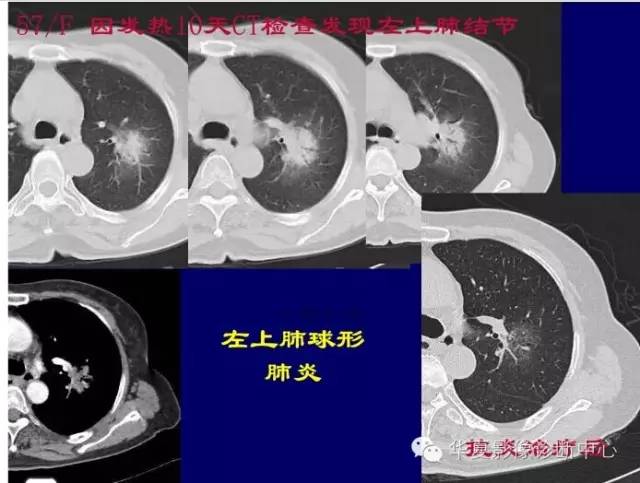

第一步:判断是否GGO

第二步:判断是否肿瘤

第三步:看边缘及内部征象

磨玻璃结节良恶性影像分析策略 混合型,边界清楚、分叶征,考虑肺癌

对于不好定的,不典型的一律建议抗炎后复查

如果不看边缘是否清楚,就好像癌肿

但是一看边缘就是炎性病变

大家记住了,边缘模糊的GGO首先考虑炎症